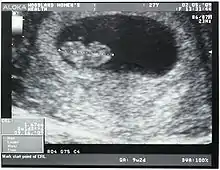

Crown-rump length (CRL) is the measurement of the length of human embryos and fetuses from the top of the head (crown) to the bottom of the buttocks (rump). It is typically determined from ultrasound imagery and can be used to estimate gestational age.

The embryo and fetus float in the amniotic fluid inside the uterus of the mother usually in a curved posture resembling the letter C. The measurement can actually vary slightly if the fetus is temporarily stretching (straightening) its body. The measurement needs to be in the natural state with an unstretched body which is actually C shaped. The measurement of CRL is useful in determining the gestational age (menstrual age starting from the first day of the last menstrual period) and thus the expected date of delivery (EDD). Different babies do grow at different rates and thus the gestational age is an approximation. Recent evidence has indicated that CRL growth (and thus the approximation of gestational age) may be influenced by maternal factors such as age, smoking, and folic acid intake. Early in pregnancy gestational age 8 weeks, it is accurate within about +/- 5 days but later in pregnancy due to different growth rates, the accuracy is less. In that situation, other parameters can be used in addition to CRL. The length of the umbilical cord is approximately equal to the CRL throughout pregnancy.